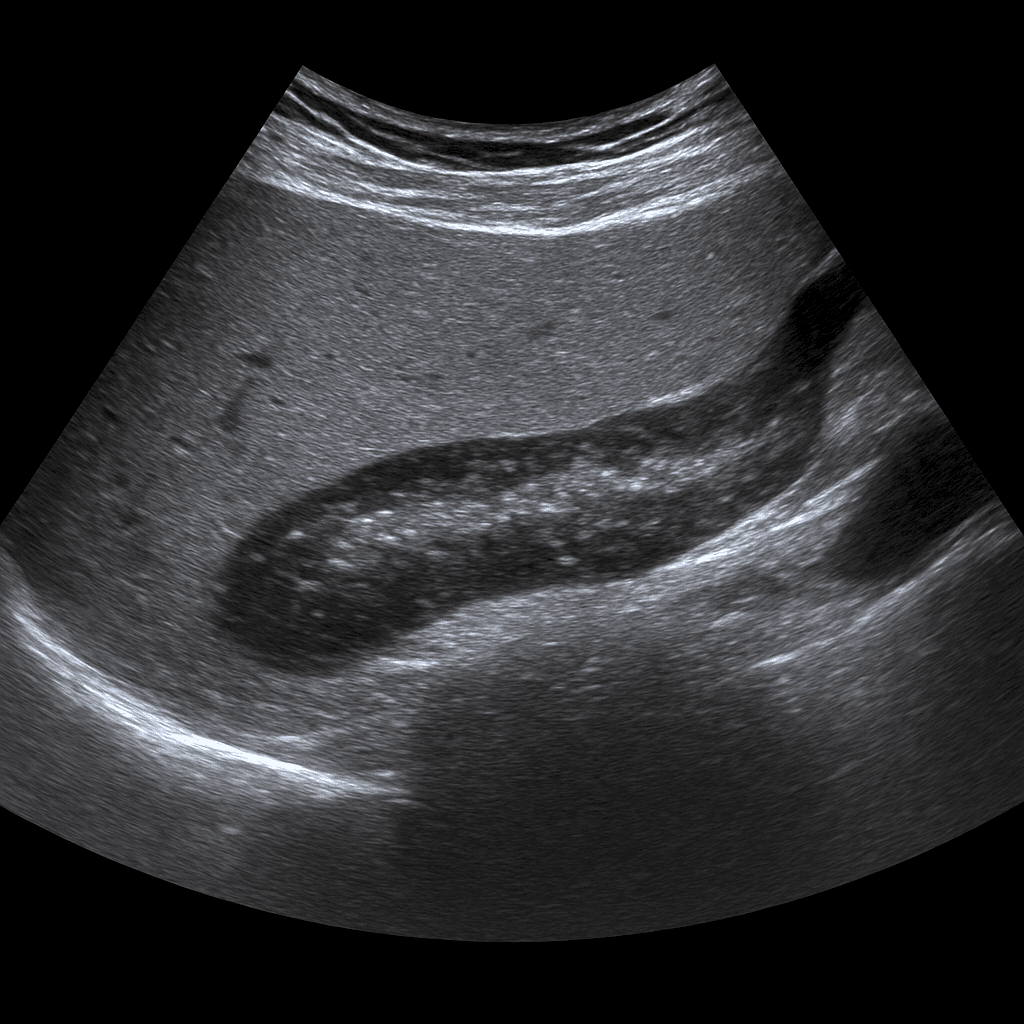

An ultrasound examination of the pancreas or (pancreas) is used to examine the size, shape, tissue structure and surrounding organs of the gland. The examination is performed by a specialist in radiology and provides real-time images that can show changes caused by inflammation, cysts, stones or tumors. Ultrasound of the pancreas is often used as the first step in the investigation of abdominal pain, jaundice or abnormal liver and pancreatic values in blood tests.

Unlike MRI and CT, which are used for more detailed mapping of glandular tissue and the urinary system, ultrasound is a fast and radiation-free method for detecting major structural changes, fluid accumulation, and surrounding inflammation. Ultrasound can sometimes be limited in the case of gas-filled intestines or deep abdominal tissue, but works excellently as an initial examination and for follow-up of known findings.

The examination is performed while you lie on your back or left side. A gel is applied to the skin and the doctor moves the ultrasound probe over the upper part of the abdomen, usually under the left rib cage. The examination usually takes 15–20 minutes. For the best image quality, it is recommended that you fast for about 4–6 hours before the examination to reduce the amount of air in the stomach and intestines.